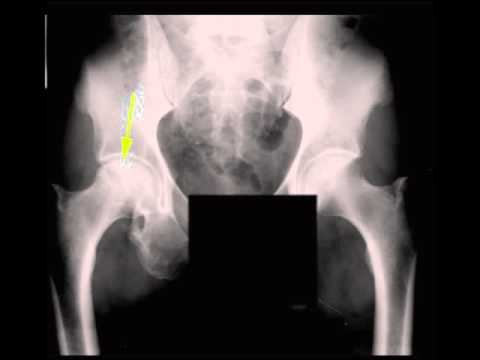

AVN Femoral Head on X ray